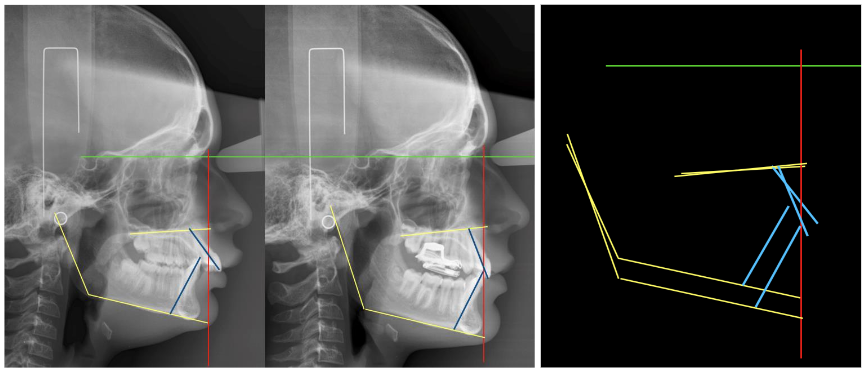

Rivero JC, et al. conducted a comparative cross-sectional study between two groups of patients (N=10) with skeletal class II, with mandibular hypoplasia, age range between 10-14 years. One group was treated with HBO (Herbst Occlusal Rod) and the other with Twin-Block. Cephalometric values were compared between T0 and T1 between both groups, to determine if there were differences in terms of mandibular advancement obtained, proclination of the mandibular incisor, mandibular posterior rotation, etc. After comparing the means with the Student T test, it was concluded that there were no statistically significant differences between the two groups (p > 0.05). HBO achieved greater advancement, but also greater proclination of the lower incisor and greater secondary mandibular posterior rotation.

The clinical procedure consists of taking records of the working models obtained by intraoral scanning of both dental arches, and of the palatal and lingual mucosa. The interocclusal record must be scanned, faithfully respecting the constructive bite in advance, with a flame-heated Godiva (jig). At 2/3 of the maximum clinical advancement.

The manufacturing is customized, to the exact measurement of each patient and each stage of treatment, by thermo-curing, stereolithography, or 3D printing. Regarding clinical management and given that physiologically a posterior and anterior disocclusion occurs between both arches, motivated by the condylar trajectory, following the articular eminences and, because it is closely related to the neuromuscular pattern of each patient (the more brachyfacial, the more posterior disocclusion), we must manage the vertical development of the posterior dentoalveolar processes and the anterior dentoalveolar dimension (incisal) depending on whether we need to intrude or extrude one or the other, at the same time that we will correct the transverse parameters correlating both arches.